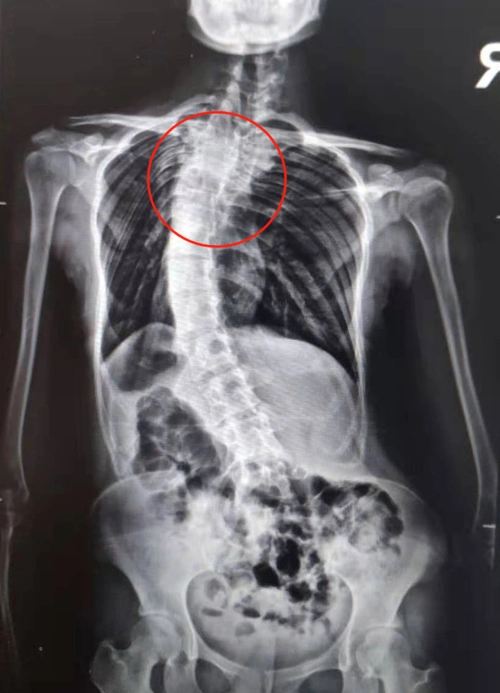

暑假将至第四期脊柱侧弯训练营即将开营

后路手术矫形治疗青少年特发性脊柱侧凸畸形附图片资料

节段在冠状面上偏离身体中线向侧方弯曲,形成一个带有弧度的脊柱畸形

脊柱侧弯八年后实施矫正手术,19 岁女孩「增高」5 厘米